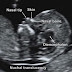

Here's an example of nuchal translucency on ultrasound So here's some very useful links (or how to be ready to respond to 'Dr. G...